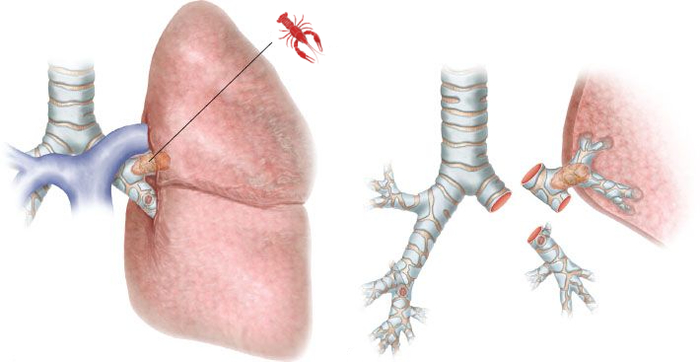

Схематично опухоль расположена вот тут:

Выше я писал, что опухоль расположена в верхнедолевом бронхе и переходит на главный бронх, следовательно, для обеспечения радикальности операции нам нужно резецировать главный бронх. Раньше в таких случаях выполняли пневмонэктомию - удаление всего лёгкого, ведь поражен главный бронх, и обеспечить радикальность операции, то есть гарантию удаления всего опухолевого объема, можно было только так. Но ведь нижняя доля лёгкого совершенно здорова, и очень жалко ее терять из-за какого-там пятимиллиметрового перехода опухоли на главный бронх. Именно для таких случаев разработаны схемы бронхопластических операций. При таких операциях мы отсекаем пораженную долю, отсекаем циркулярный фрагмент главного бронха на достаточном расстоянии от края опухоли, а его (главного бронха) остаток вшиваем в здоровый нижнедолевой бронх, как труба в трубу. Тем самым обеспечивается и радикальность операции и сохраняется целая половина легкого.

Схематически операция выглядит вот так: